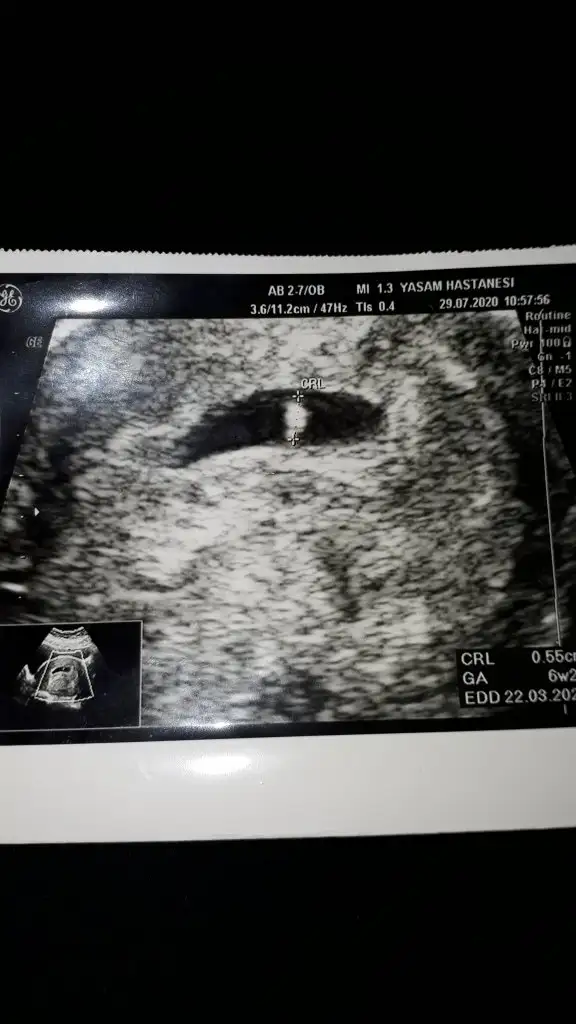

8+3 geç bu teori için yolk saç ne tarafta oluştuysa ona göre yorum yapmak lazım 6 veya 7 haftalık olmalıIkra meyra canım lütfen o güzel tahminlerinden bana da yapar mısın☺ 8+3 günlük karından usg

Karından bakıldı ise kız gibi ama en iyi 11 12 13 haftalarrica etsem ııkr meyra benimkilere yorum yaparmisin

Teşekkür ederim ıkra meyra. Evet karından bakıldı.ikili test için gittiğimde tekrar usg atarımKarından bakıldı ise kız gibi ama en iyi 11 12 13 haftalar